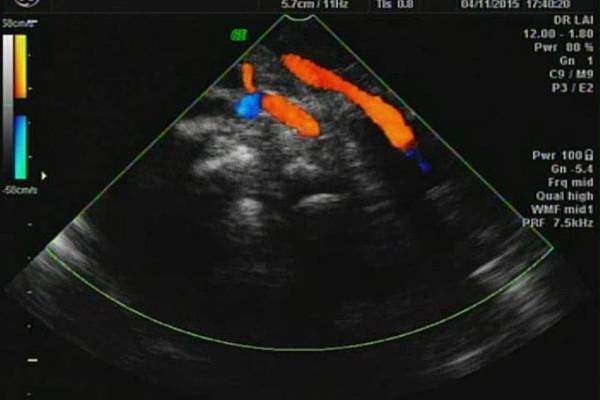

有一對夫妻因為我之前迷走性右側鎖骨下動脈(ARSA)的診斷而選擇孕兒診所,先生告知因為曾經有一個產前被我診斷ARSA的個案在他們醫院出生,他們花很久的時間才證實新生兒有ARSA,他覺得我很厲害,我有點不好意思,其實對專家而言,胎兒時期要診斷ARSA比新生兒容易,原因是胎兒時期超音波下,這條血管可以很清楚的被看到,它是從主動脈出來經過氣管的後面由左側繞到右側(附圖 1.),但是新生兒心臟超音波要看這條血管有困難,因為氣管擋住這條血管,醫師只能靠主動脈的第一個分支(brachiocephalic artery)沒有呈現 y 的特徵(附圖 2.),所謂 y 是brachiocephalic artery正常是會分出兩個分支(附圖 3.4.),一個是right common carotid artery,另一個是right subclavian artery,如果有迷走性右側鎖骨下動脈( ARSA ),就不會有正常的right subclavian artery,所以在新生兒的右頸部就不會看到 y的特徵,新生兒要直接看到迷走性右側鎖骨下動脈( ARSA)這條血管真的要花很多的時間(參考第51篇文章)。